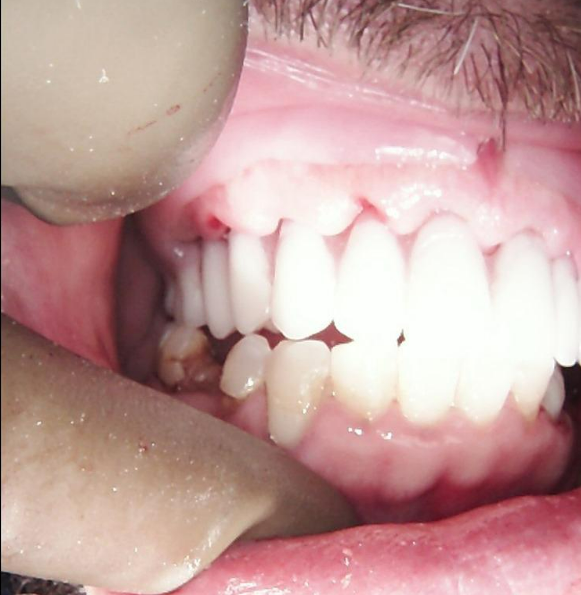

Currently, the patient is wearing the provisional PMMA prosthesis. He is attending regular professional hygiene appointments and adhering to a strict home care regimen. This transitional period allows for the evaluation of the function and esthetics of the PMMA prosthesis, so that any necessary adjustments can be made before fabricating the final restoration, ensuring an optimal outcome.

The patient’s appearance at this stage demonstrates a natural and harmonious result.